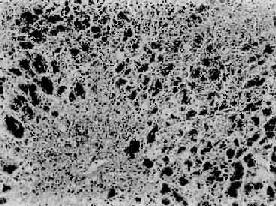

暴發性肝功能衰竭病理妊娠期急性脂肪肝、Reye綜合徵等肝病理特點為肝細胞內線粒體嚴重損害,而致代謝功能失常。肝小葉至中帶細胞增大,胞漿中充滿脂肪空泡,呈蜂窩狀,無大塊肝細胞壞死。肝縮小不如急性重型肝炎顯著。